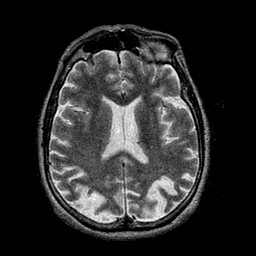

Alzheimer's disease: overlay -- Slice #31

[Home][Help][Clinical] Slice 31